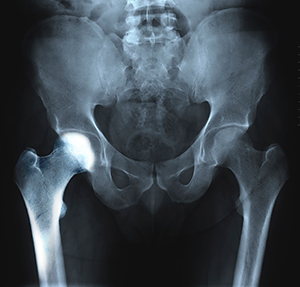

The hip joint is a ball-and-socket joint. A part of the pelvis bone known as the acetabulum forms the socket and the upper end of the femur, known as the femoral head, forms the ball. In patients with transient osteoporosis of the hip, the femoral head loses its density and strength and becomes more prone to breaking.

You will also be recommended to undergo imaging studies such as X-rays, CT scans, MRIs, or nuclear scans to further document transient osteoporosis of your hip.